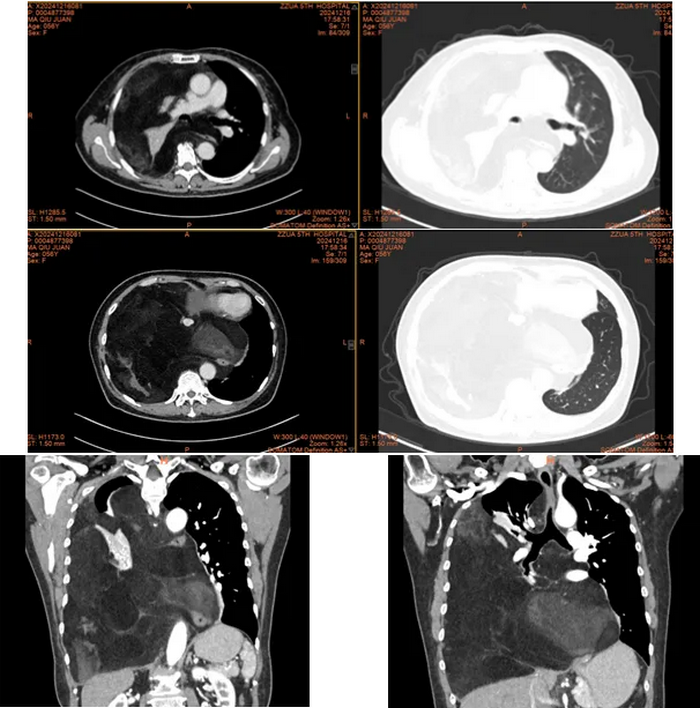

检查发现,马女士右侧胸腔及纵隔内见巨大团片状低密度影,累及左侧胸腔致心脏大血管及气管向左侧胸腔偏移,以脂肪密度为主。肿瘤累及气管、左右主支气管、上腔静脉及主动脉外膜、部分心包、左右下肺静脉,累及并包埋食管及下腔静脉,右肺受压不张。而接下来的手术堪称一场惊心动魄的生命之战。

经过胸外科高兴才主任团队、麻醉科胡强夫主任团队等科室充分准备,输血科魏明主任团队积极备血后,手术按计划如期进行,选择右胸第6肋后外侧切口进胸,因肿瘤体积巨大,占满胸腔,纵隔移位,累及上纵隔、中纵隔、后纵隔,并包绕主动脉及上、下腔静脉、食管。手术空间狭窄,视野受限,术中联合胸腔镜辅助手术,行胸腔及纵隔巨大肿瘤满意切除、心包部分切除。